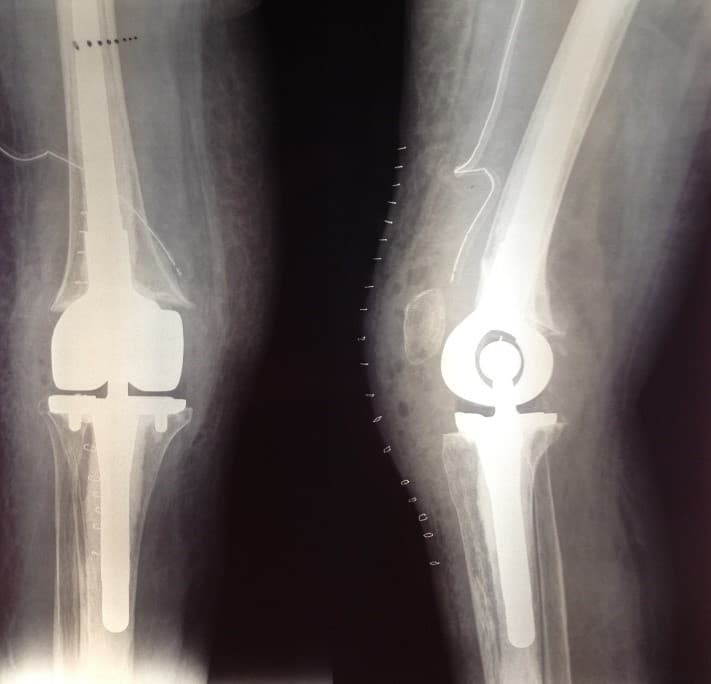

Үе дайрсан ясны анхдагч хавдар, ясны дутмагшлын үед хийгдэх мэс засалimg17Үе дайрсан ясны анхдагч хавдар, ясны дутмагшлын үед хийгдэх мэс засалimg18

Зураг 1. Сэргээн засах мэс заслын өмнөх рентген зураг. Эгц урд, хажуугаас авсан байдал.

Энэ тохиолдолд үений шөрмөсөн холбоос хэвийн хадгалагдаж үлдсэн байсан. Хиймэл үе - ястай тогтвортой сайн бэхлэгдэх нөхцлийг хангах чөмөгт гол руу орсон уртасгагч – extension stem-тэй хиймэл үе.